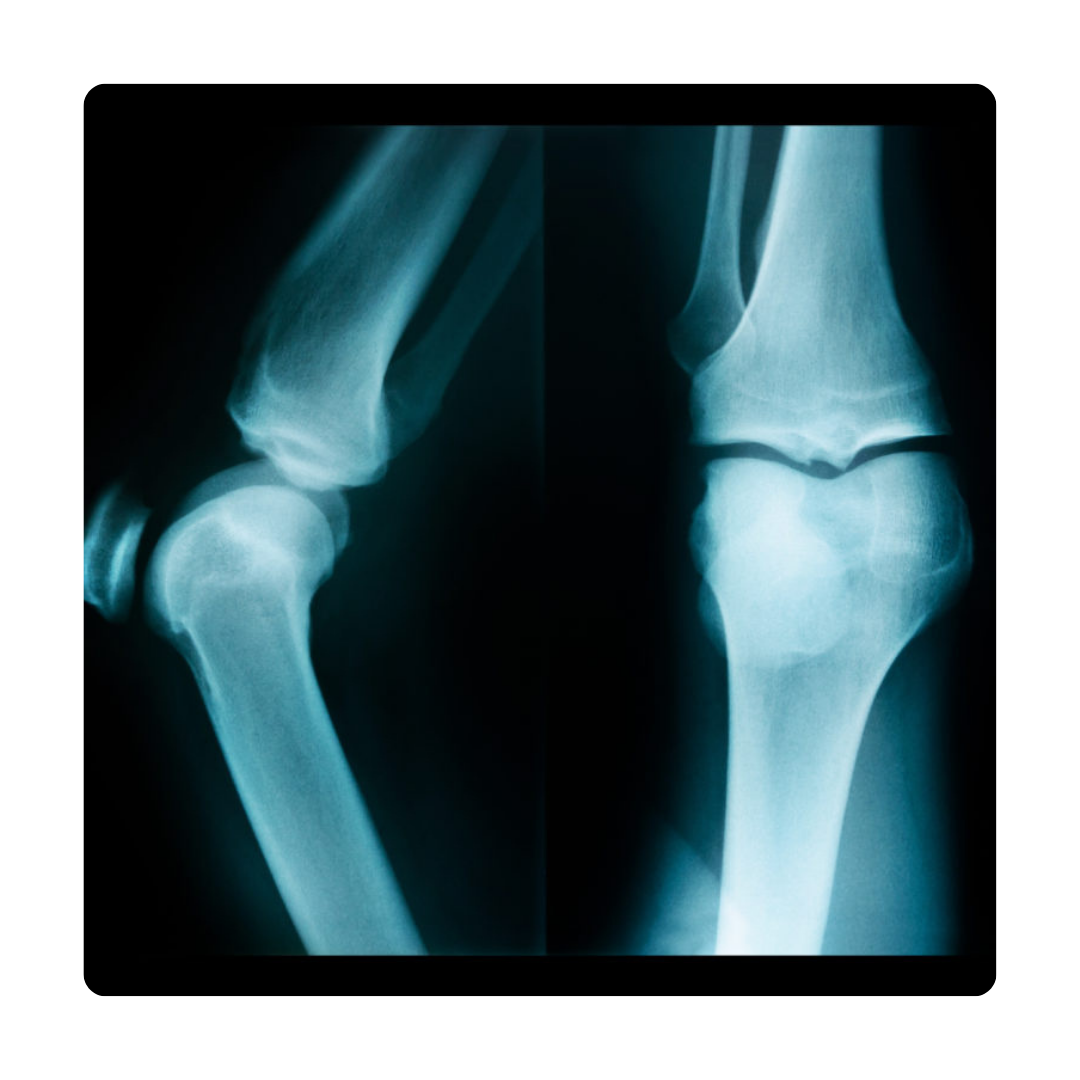

Bone and The Joint Surgery

Orthopedic Trauma Care

- Traumatic Injury Surgery: Emergency surgery for fractures, dislocations, and ligament tears.